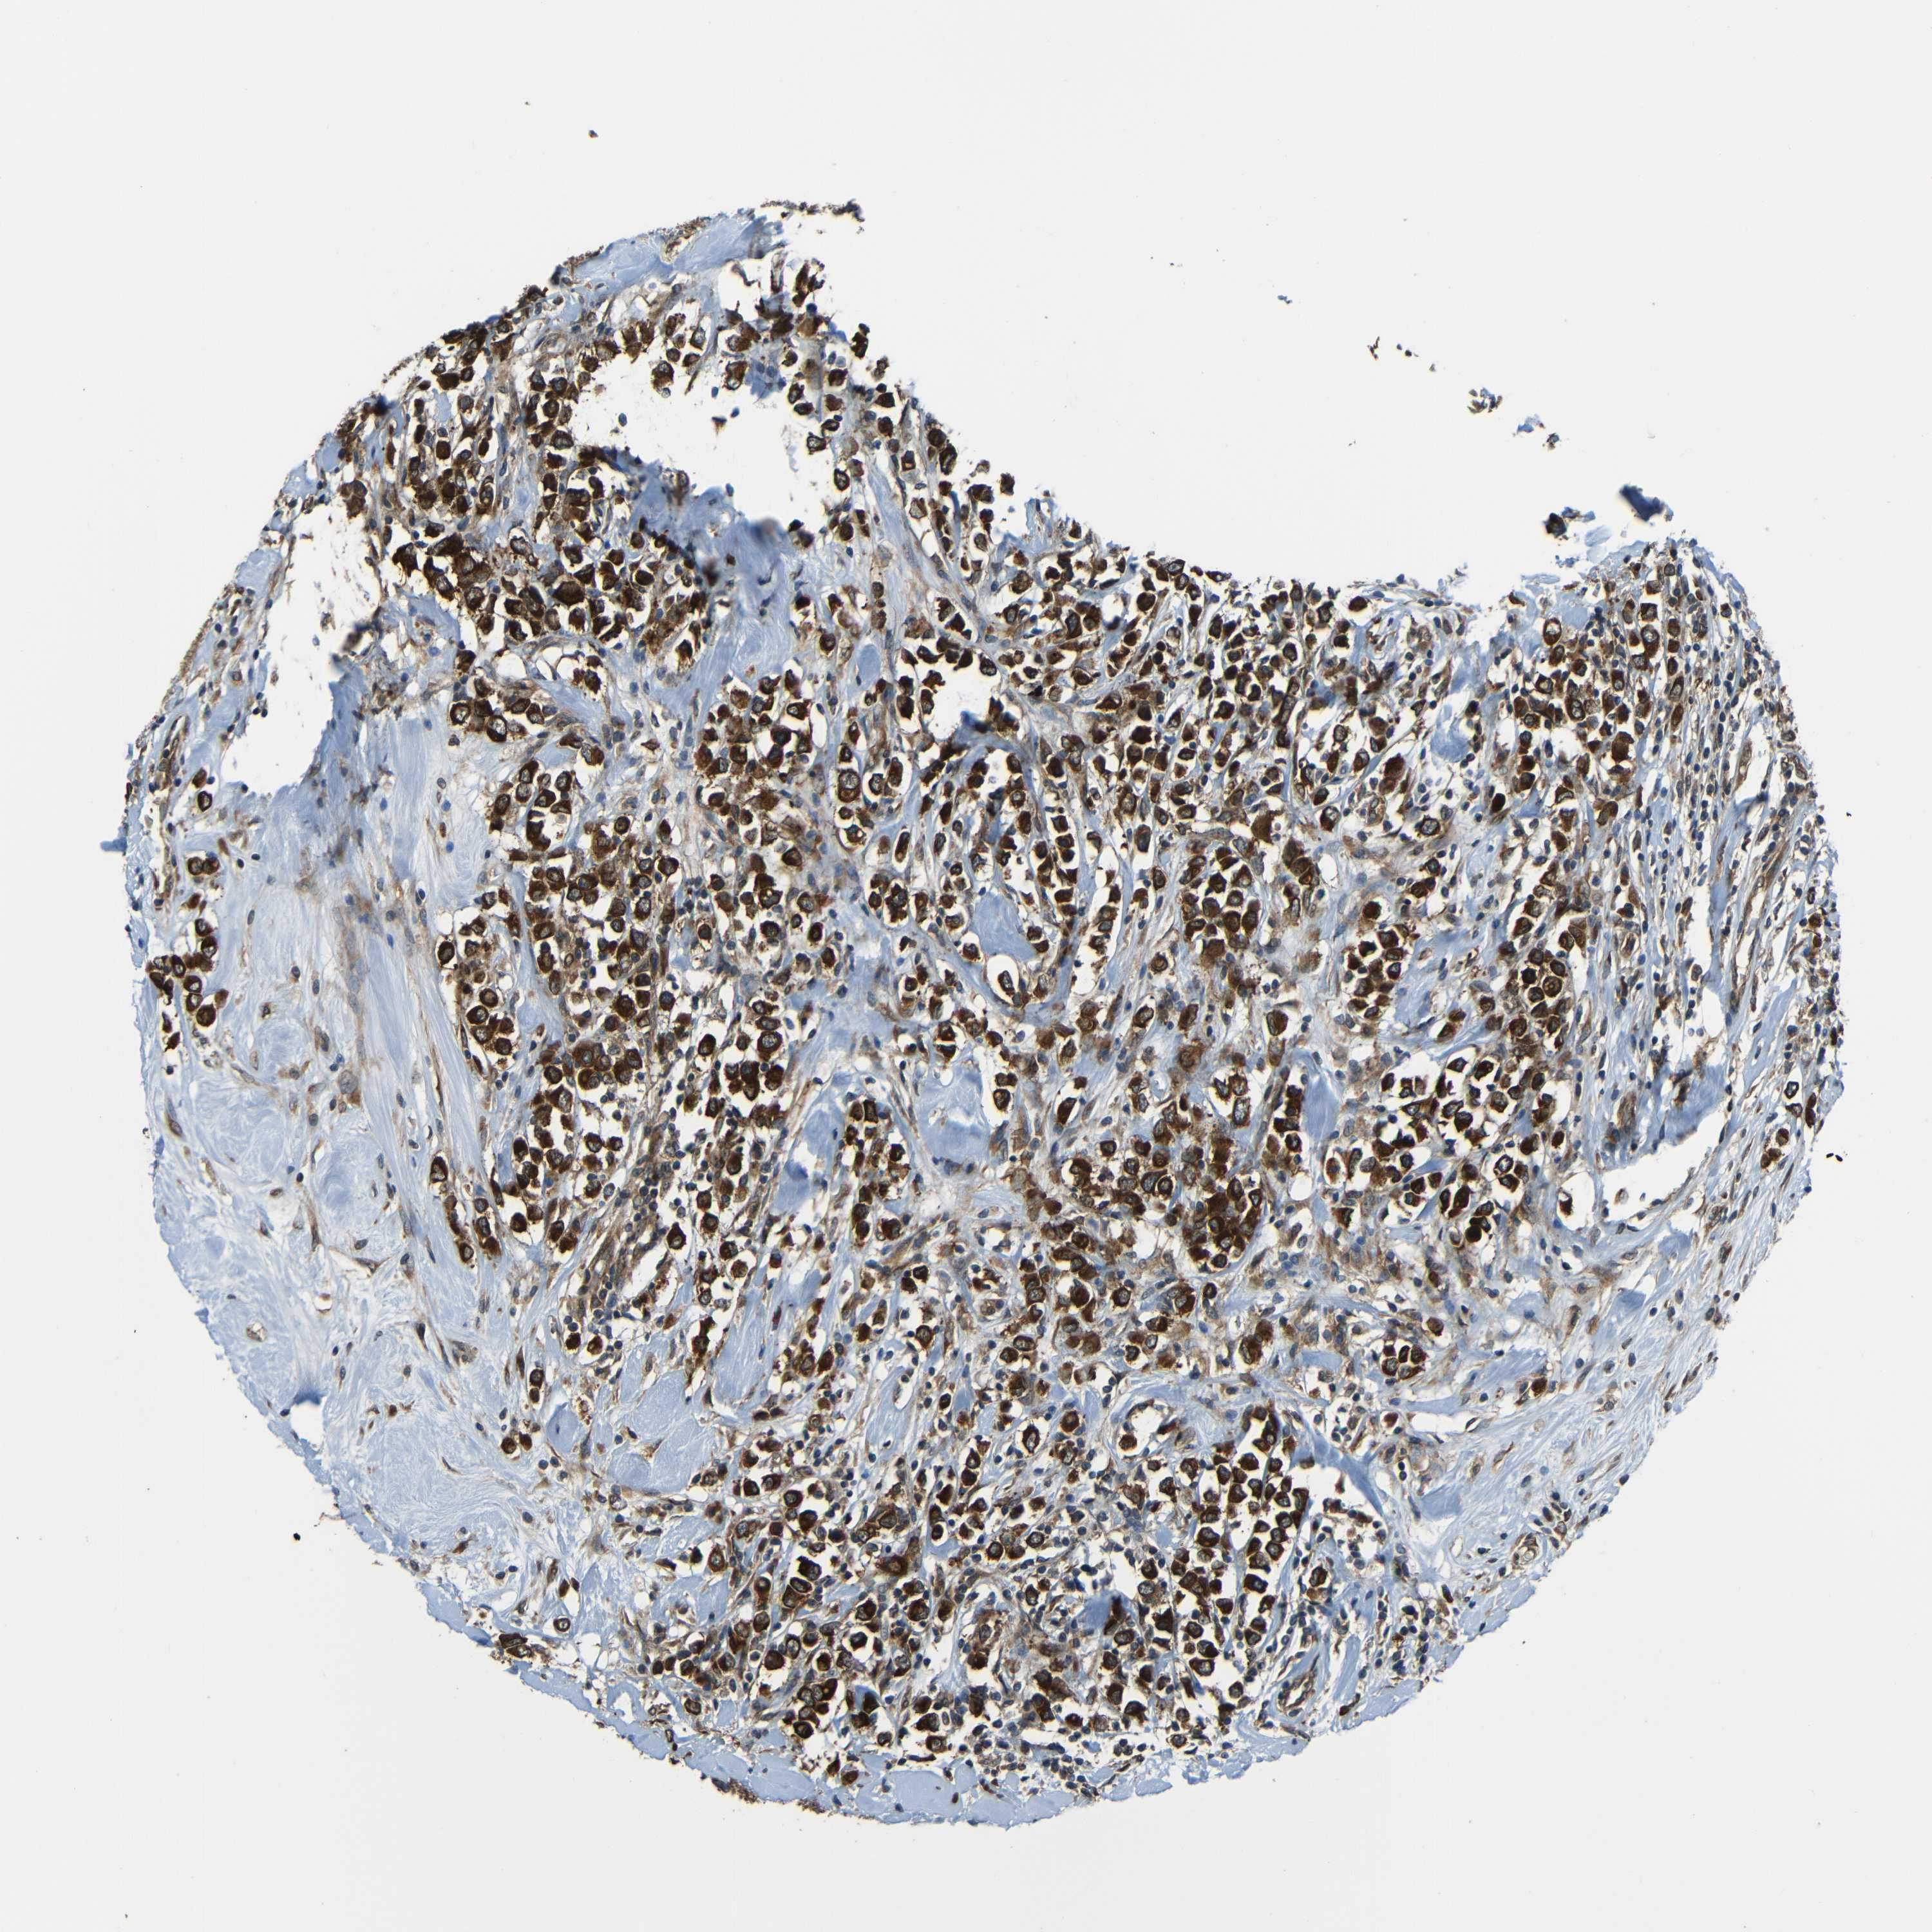

CANCER BREAST CANCER Show tissue menu

BRCA TCGA BRCA VALIDATION PROTEIN EXPRESSION

VAPB is potential prognostic, high expression is unfavorable in Breast Invasive Carcinoma (TCGA)